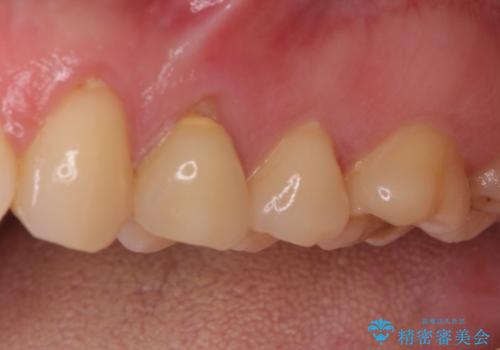

- 食事などで咬みこむと痛みを感じるとのことで来院された患者様です。

診査の結果、既に歯の神経は失活しており、レントゲンより根尖部に病変を認めました。

根管治療を行った後にオールセラミッククラウンにて補綴することとしました。